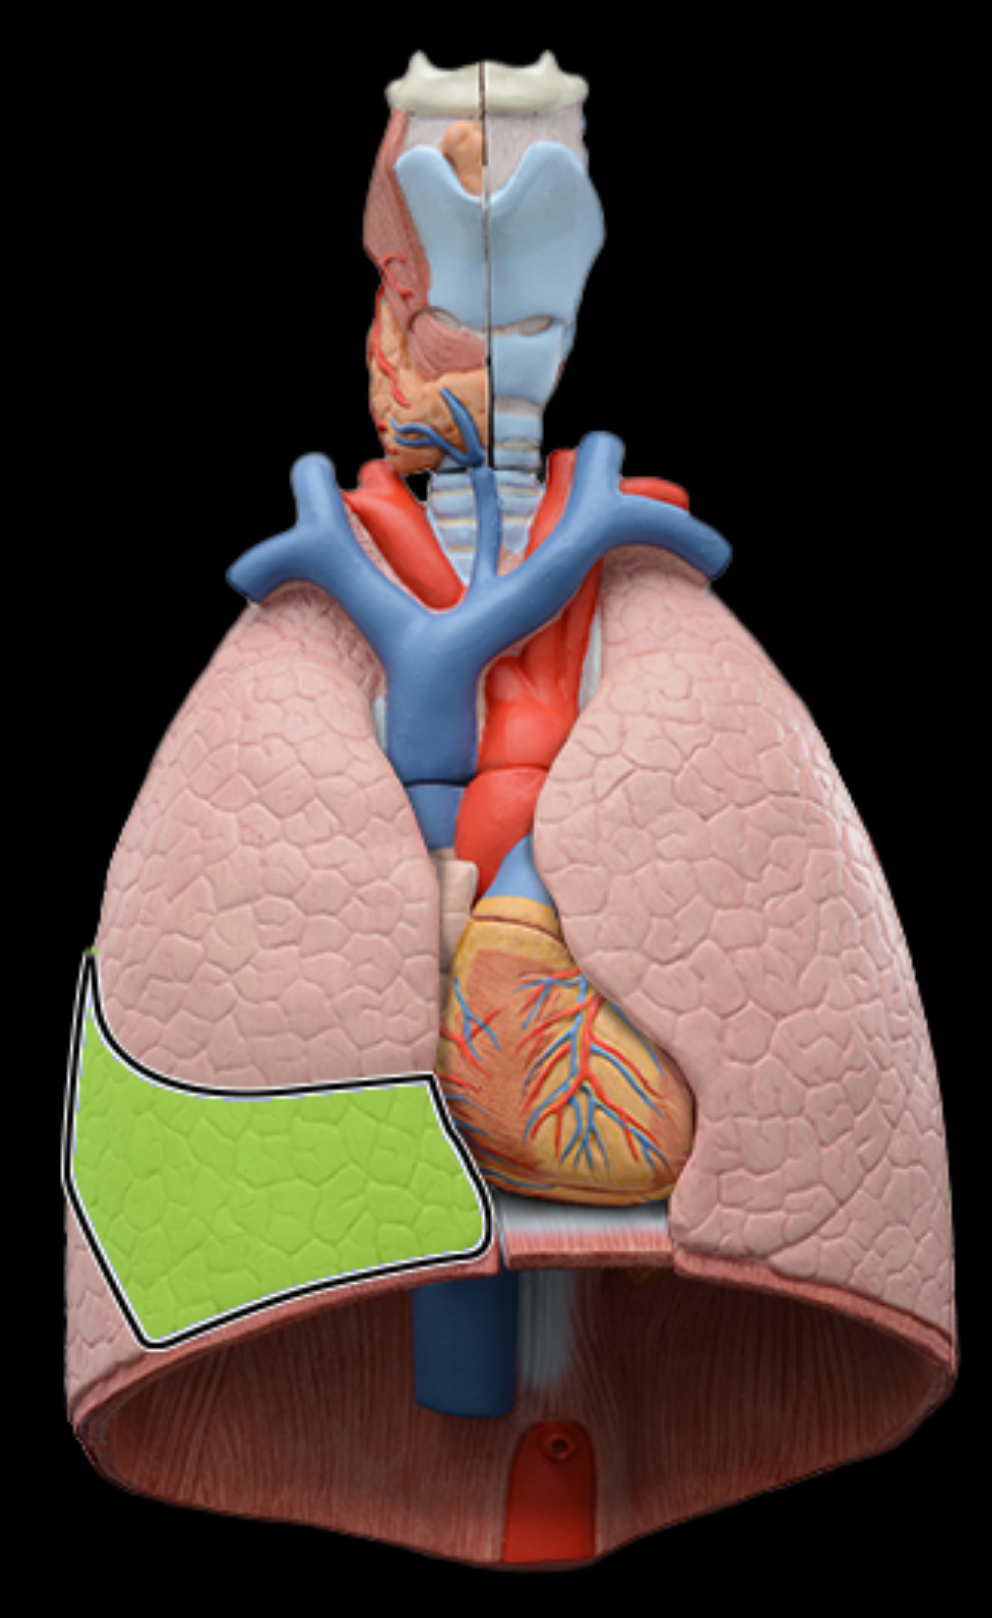

Superior, lobe of right lung

middle lobe of right lung

inferior lobe of right lung

Horizontal fissures of right lung

oblique fissures of right lung

Superior lobe of left lung

inferior lobe of left lung

oblique fissure of left lung

cardiac notch